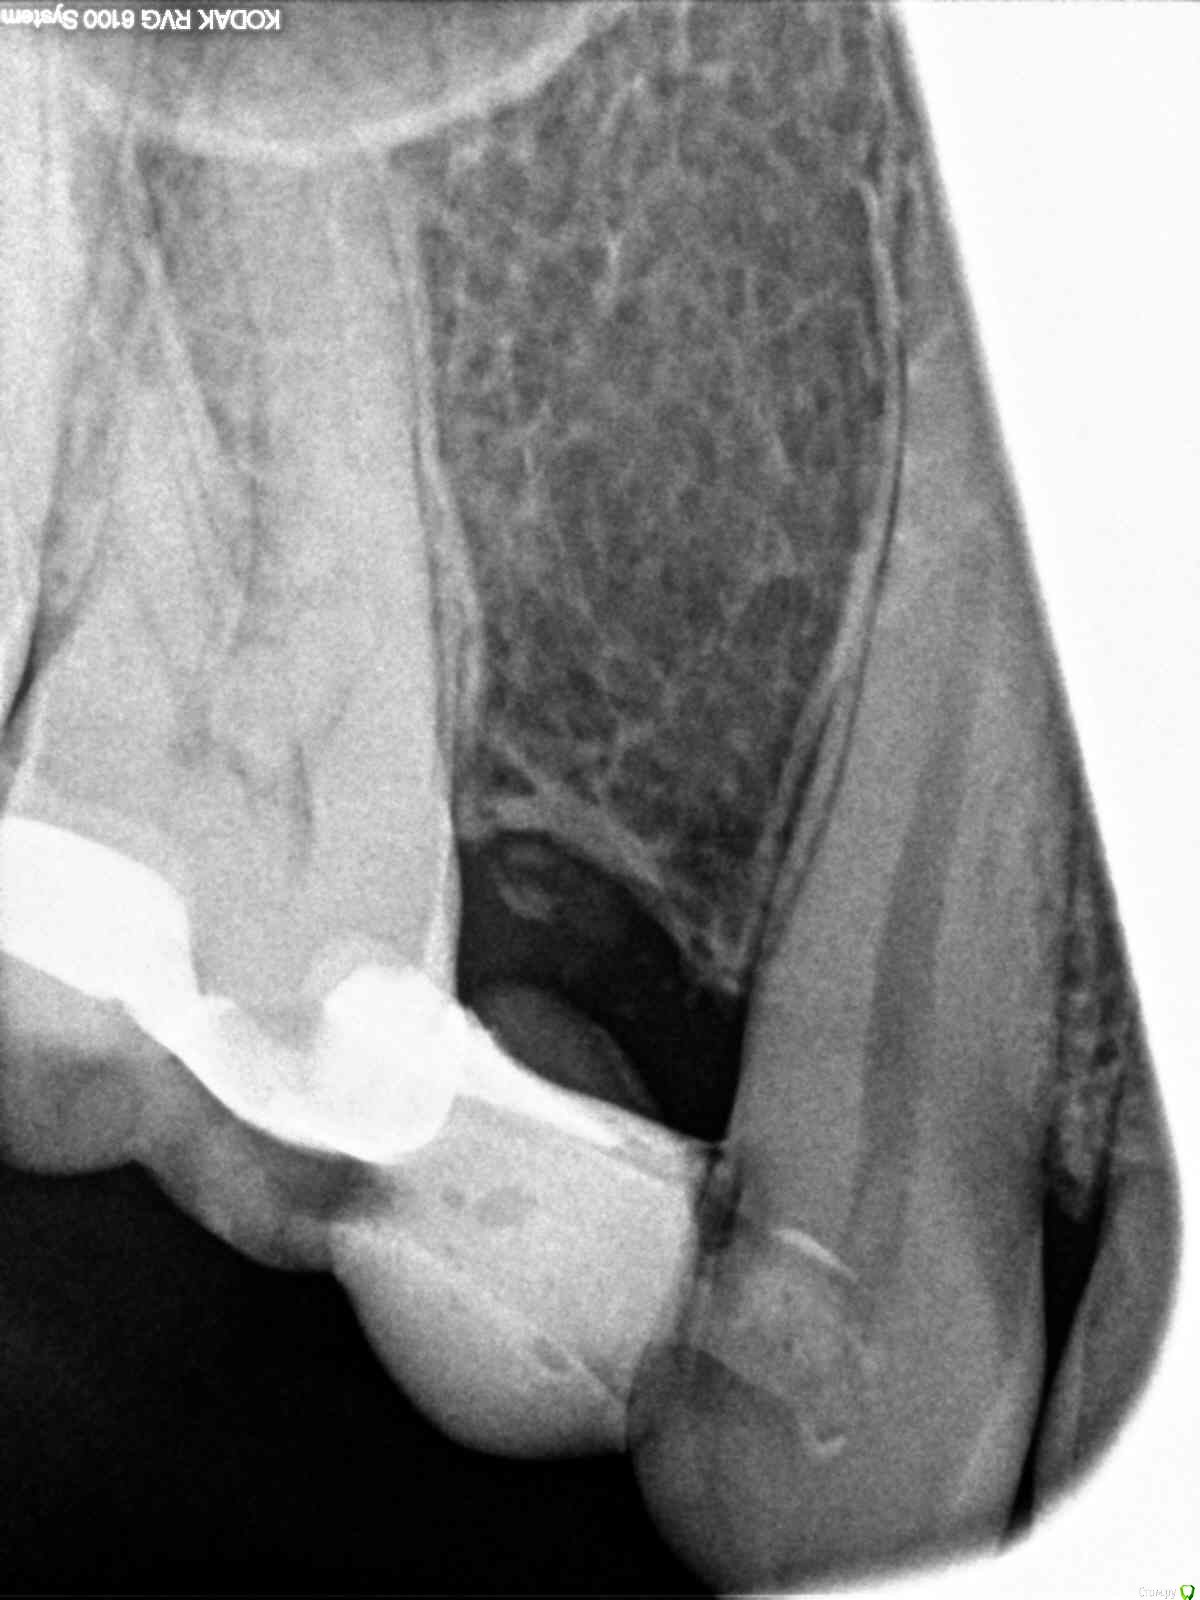

milina Опубликовано 9 декабря, 2016 Поделиться Опубликовано 9 декабря, 2016 (изменено) Здравствуйте! Очень нужна ваша помощь. Обратилась в стоматологию по поводу несильной ноющей боли в 6 верхнем зубе и стало больно надкусывать этим зубом. Два первых снимка сделаны за 2 недели до этого. На зубе крепится мерилендовсий протез, поставленный много лет назад. Стоматолог удалил нерв, он был по ее словам уже погибшим, белого цвета. 3 канала прочистили, заложили пасту с кальцием.После прохождения действия анестезии, стал очень болеть зуб, даже при касании его языком, чувство распирания, кусать вообще невозможно было. На след. день я обратилась в клинику, другой доктор снял временную пломбу, промыл каналы и отправил домой полоскать содой и солью. Стало легче, но меня еще беспокоила боль при пальпации слизистой в районе верхушки корня. Еще на следующий день мой стоматолог посмотрела, сказала, что возможно у меня реакция на пасту, при прочистке каналов болезненность была только в одном из них на верхушке. Заложила пасту с гвоздичным маслом и поставила временную пломбу. Боль стала потихоньку снижаться на следующий день и появился постоянный привкус этого масла во рту. Через три дня снова посетила стоматолога, промыли опять каналы, по ее словам все чисто, ни гноя, ни сукровицы. Так же присутствовала болезненность в одном канале. Заложила какое-то лекарство, стало сразу очень больно, промыли, заложили другое лекарство, к сожалению, не спросила, какое именно. Врачу я сообщила, что присутствует боль при пальпации над корнем и появилось под слизистой небольшое уплотнение, миллиметра два. При внешнем осмотре ничего не видно. Сделали снимок, качество ужасное, но врач сказала, что ничего там плохого не видит., на мой взгляд, на нем вообще ничего не видно, еще и накладывается гайморова пазуха. После приема стала чувствовать боль в зубе при ходьбе, когда топаешь ногой, или при похлопывании по голове, все отдается в зубе. Прошло два дня, сильных болей нет, но зуб чувствую постоянно, при надкусывании болезненность, присутствует чувство распирания, терпимая боль при пальпации слизистой в районе корня и так же присутствует уплотнение под слизистой. Помимо этого сегодня обнаружила, что со стороны больного зуба увеличились лимфоузлы под ухом и под нижней челюстью.Температура сейчас в районе 37, такая же была и до лечения 37-37.3. Уважаемые доктора, как вы считаете, положительная динамика присутствует или состояние ухудшается и мне нужно обратиться к другому специалисту. Меня волнуют эта шишечка под слизистой и лимфоузлы. Как бы хуже не стало. Изменено 9 декабря, 2016 пользователем milina Ссылка на комментарий